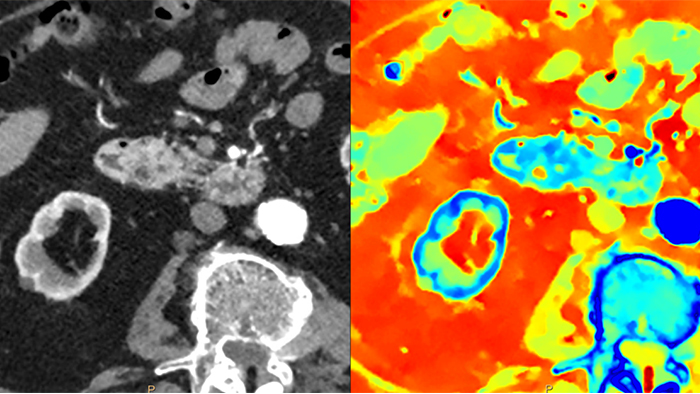

Multi-Energy-CT

2016: Philips - das erste CT-System mit Spektraldetektor

CT-Systeme mit Spektraldetektor machten konventionelles CT zu quantitativem CT. Die zweite Generation des Philips Spectral CT 7500 erhielt den Aunt Minnie Award for Best New Radiology Device in 2021.

Im Gegensatz zur klassischen CT-Untersuchung beinhalten Spektraldetektor-CT-Daten immer auch spektrale Informationen, ohne spezielle Vorkehrungen oder zusätzliche Vorbereitungen. Das bedeutet, Sie können die Spektraldaten jeder Untersuchung auch retrospektiv mit unterschiedlichen Diagnosetools analysieren. Sie können beispielsweise die monoenergetischen Energielevel anpassen oder Z-effektive Bilder erhalten.

Der Spektraldetektor absorbiert und differenziert gleichzeitig die hohe und niedrige Energie eines einzigen polyenergetischen Röntgenstrahls. Spektralergebnisse werden in einem einzigen Scan ohne Einstellung separater Scan-Modi erfasst.

Ein CT-System mit Spektraldetektor absorbiert und differenziert gleichzeitig die hohe und niedrige Energie eines einzigen polyenergetischen Röntgenstrahls auf Detektorebene.